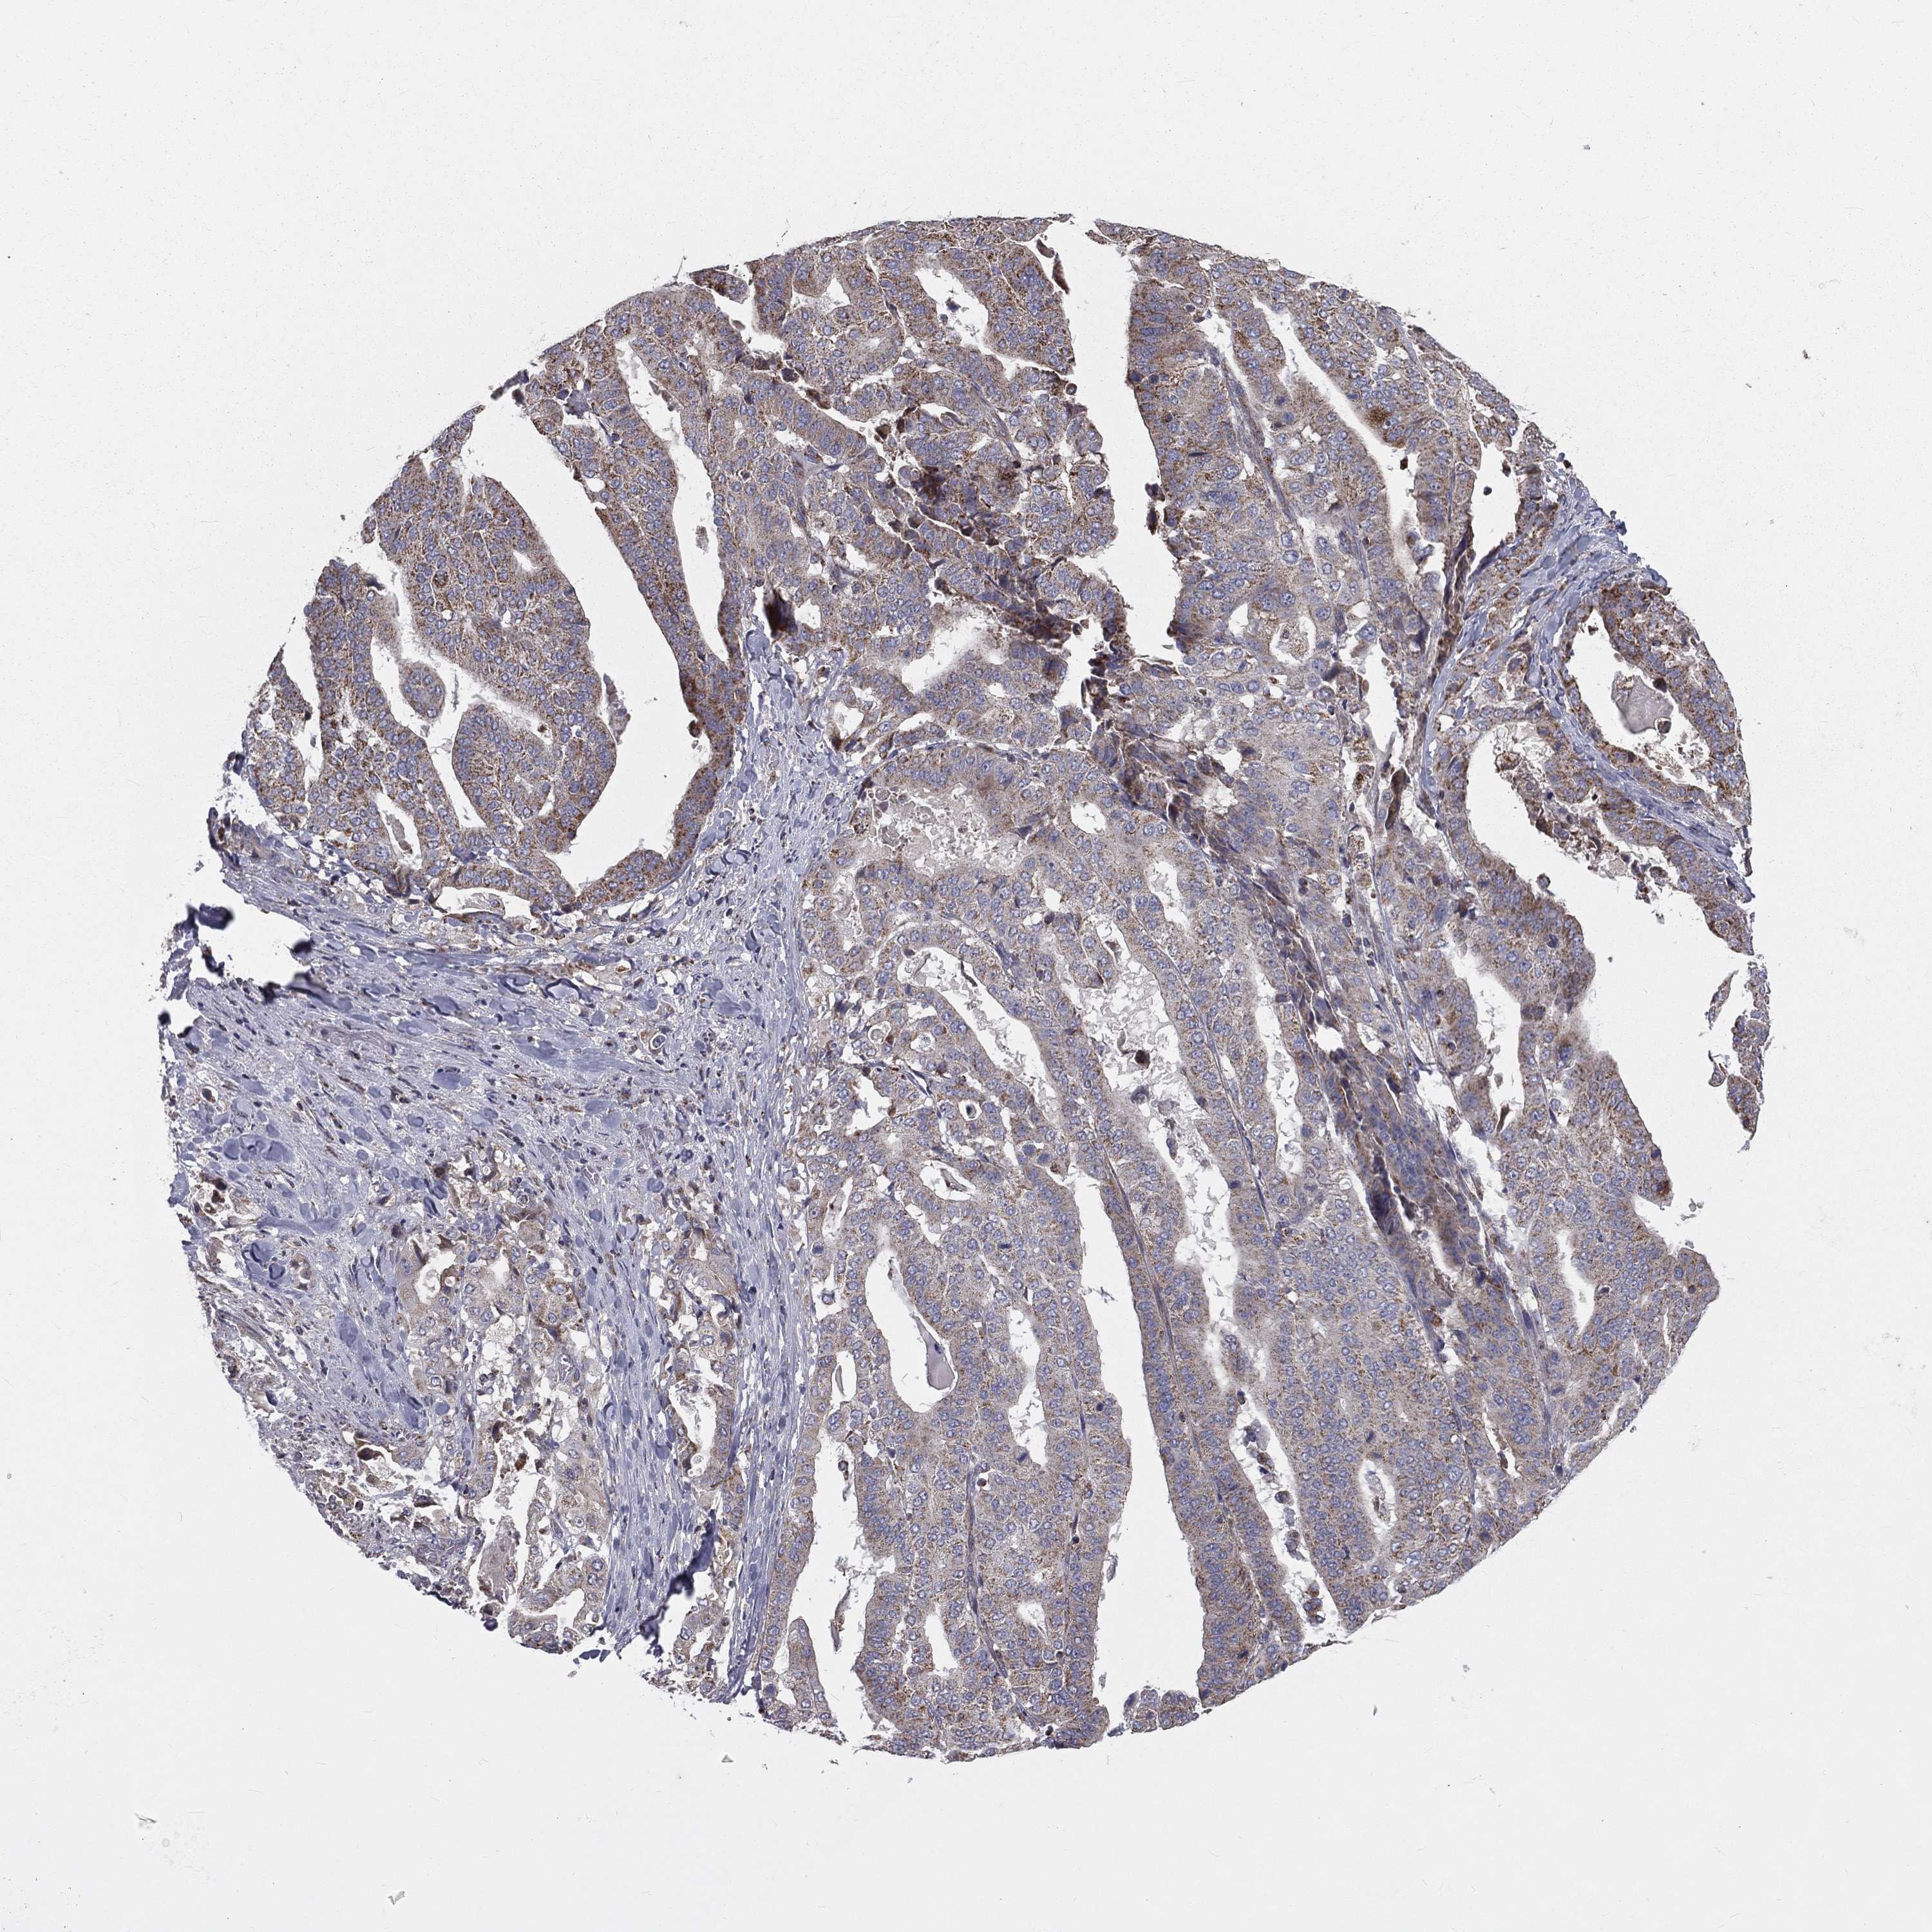

STOMACH CANCER - Protein expressioni

A mouse-over function shows sample information and annotation data. Click on an image to view it in a full screen mode. Samples can be filtered based on level of antibody staining by selecting one or several of the following categories: high, medium, low and not detected. The assay and annotation is described here.

Note that samples used for immunohistochemistry by the Human Protein Atlas do not correspond to samples in the TCGA dataset.

Antibody stainingi

Antibody staining in the annotated cell types in the current human tissue is reported as not detected, low, medium, or high, based on conventional immunohistochemistry profiling in selected tissues. This score is based on the combination of the staining intensity and fraction of stained cells.

Each image is clickable and will lead to virtual microscopy that enables deeper exploration of all samples and also displays staining intensity scores, fraction scores and subcellular localization as well as patient and tissue information for each sample.

Antibody HPA044620

Antibody HPA058621

Staining

High

Medium

Low

Not detected

Intensity

Strong

Moderate

Weak

Negative

Quantity

>75%

75%-25%

<25%

None

Location

Nuclear

Cytoplasmic/membranous

Cytoplasmic/membranous,nuclear

Adenocarcinoma, NOS

Adenocarcinoma, High grade